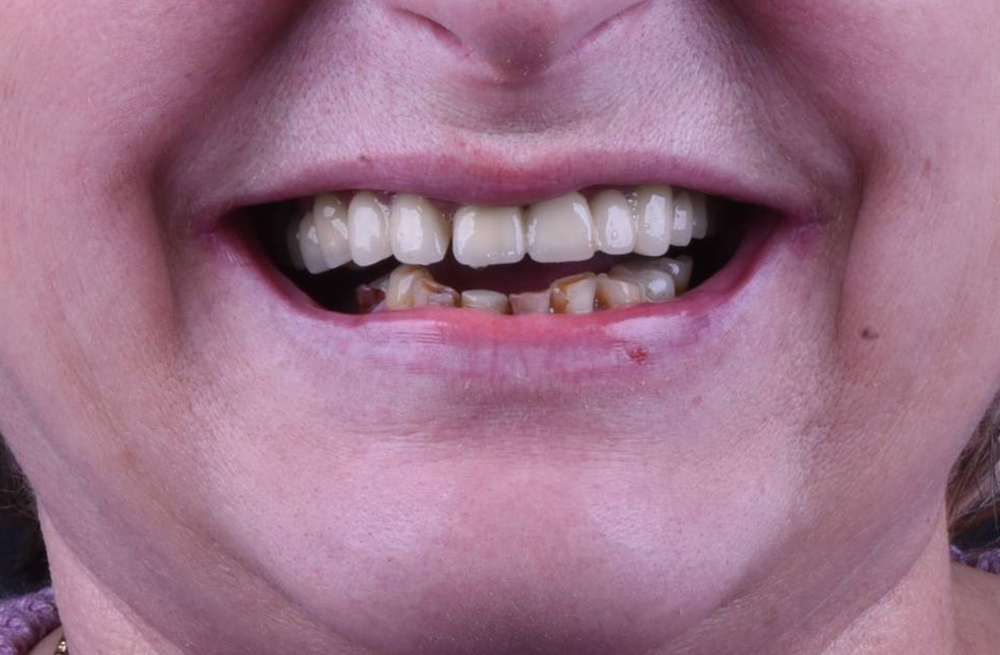

Тотальное восстановление зубов обеих челюстей